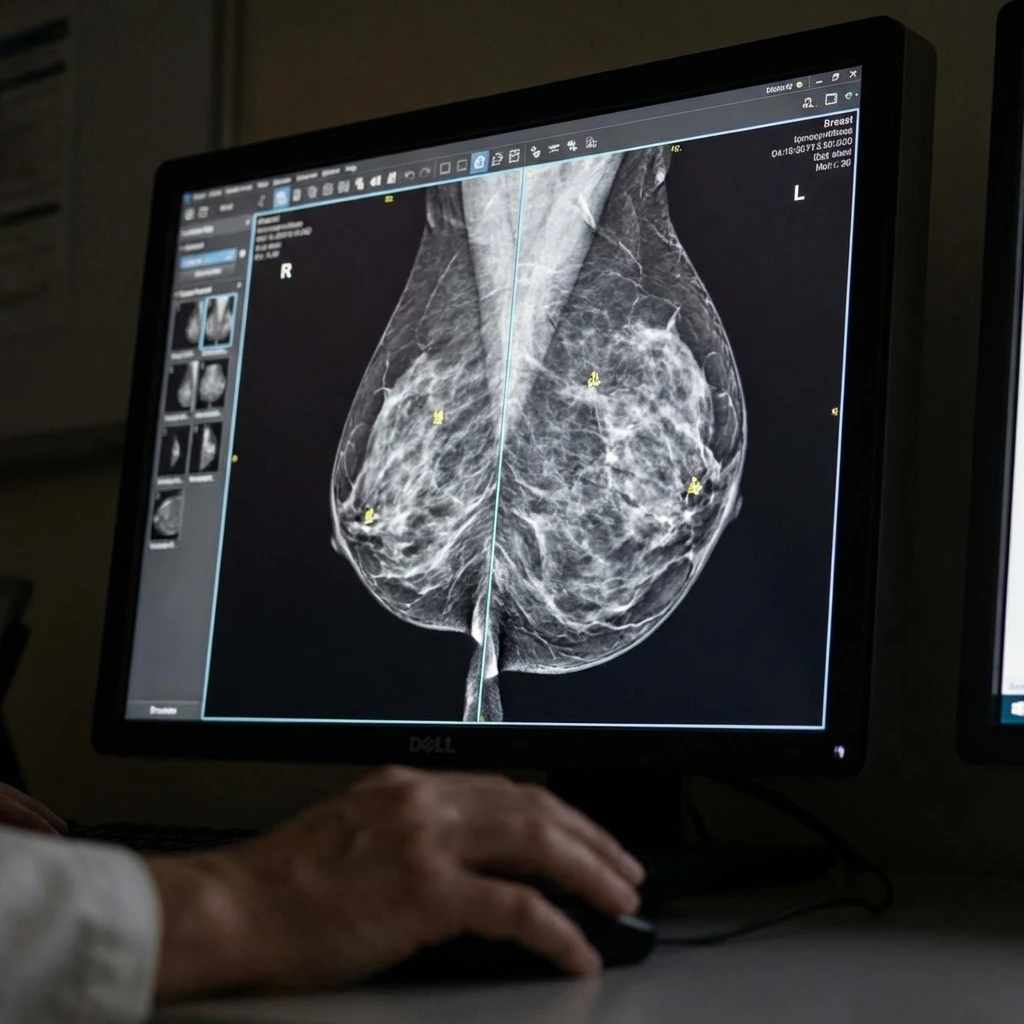

Το πρώτο σύστημα μαστογραφίας που ενέκρινε ο FDA για 3D απεικόνιση. Ανιχνεύει 20-65% περισσότερους διηθητικούς καρκίνους από την 2D μαστογραφία. Προσφέρει εξαιρετική ευκρίνεια μέσω της τεχνολογίας Τομοσύνθεσης, εντοπίζοντας βλάβες που δεν είναι ορατές στις συμβατικές 2D μαστογραφίες.

Η κεφαλή του μαστογράφου κινείται σε τόξο λαμβάνοντας πολλαπλές εικόνες, οι οποίες ανασυντίθενται τρισδιάστατα. Αυτό επιτρέπει στους ιατρούς να εξετάζουν τον ιστό του μαστού σε λεπτές τομές, εξαλείφοντας τις επιπροβολές.

Hologic Selenia Dimension 3D

Προληπτικός έλεγχος με την υψηλότερη διαγνωστική ακρίβεια για γυναίκες με πυκνούς μαστούς.